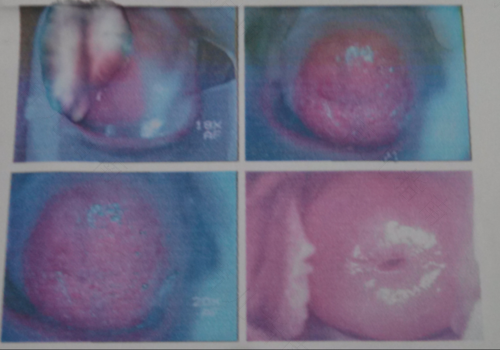

很多女性都忽视了每年的身体检查,如果出现某些宫颈疾病的话,长久下去便会引发严重的妇科炎症。只有做好定期检查,积极配合医生的治疗,才会有效避免炎症的出现。那么,宫颈轻糜严重吗?

不严重,发现有轻度的宫颈糜烂,这个没必要紧张。因为绝大多数的宫颈糜烂是一种假性糜烂,是由于雌激素水平比较高造成的柱状上皮外移。如果经常出现小腹疼痛,可以去医院做宫颈TCT和HPV检查,如果检查没有什么问题,就不是宫颈的原因造成的。如果检查有宫颈炎症,可以采取阴道内用药。